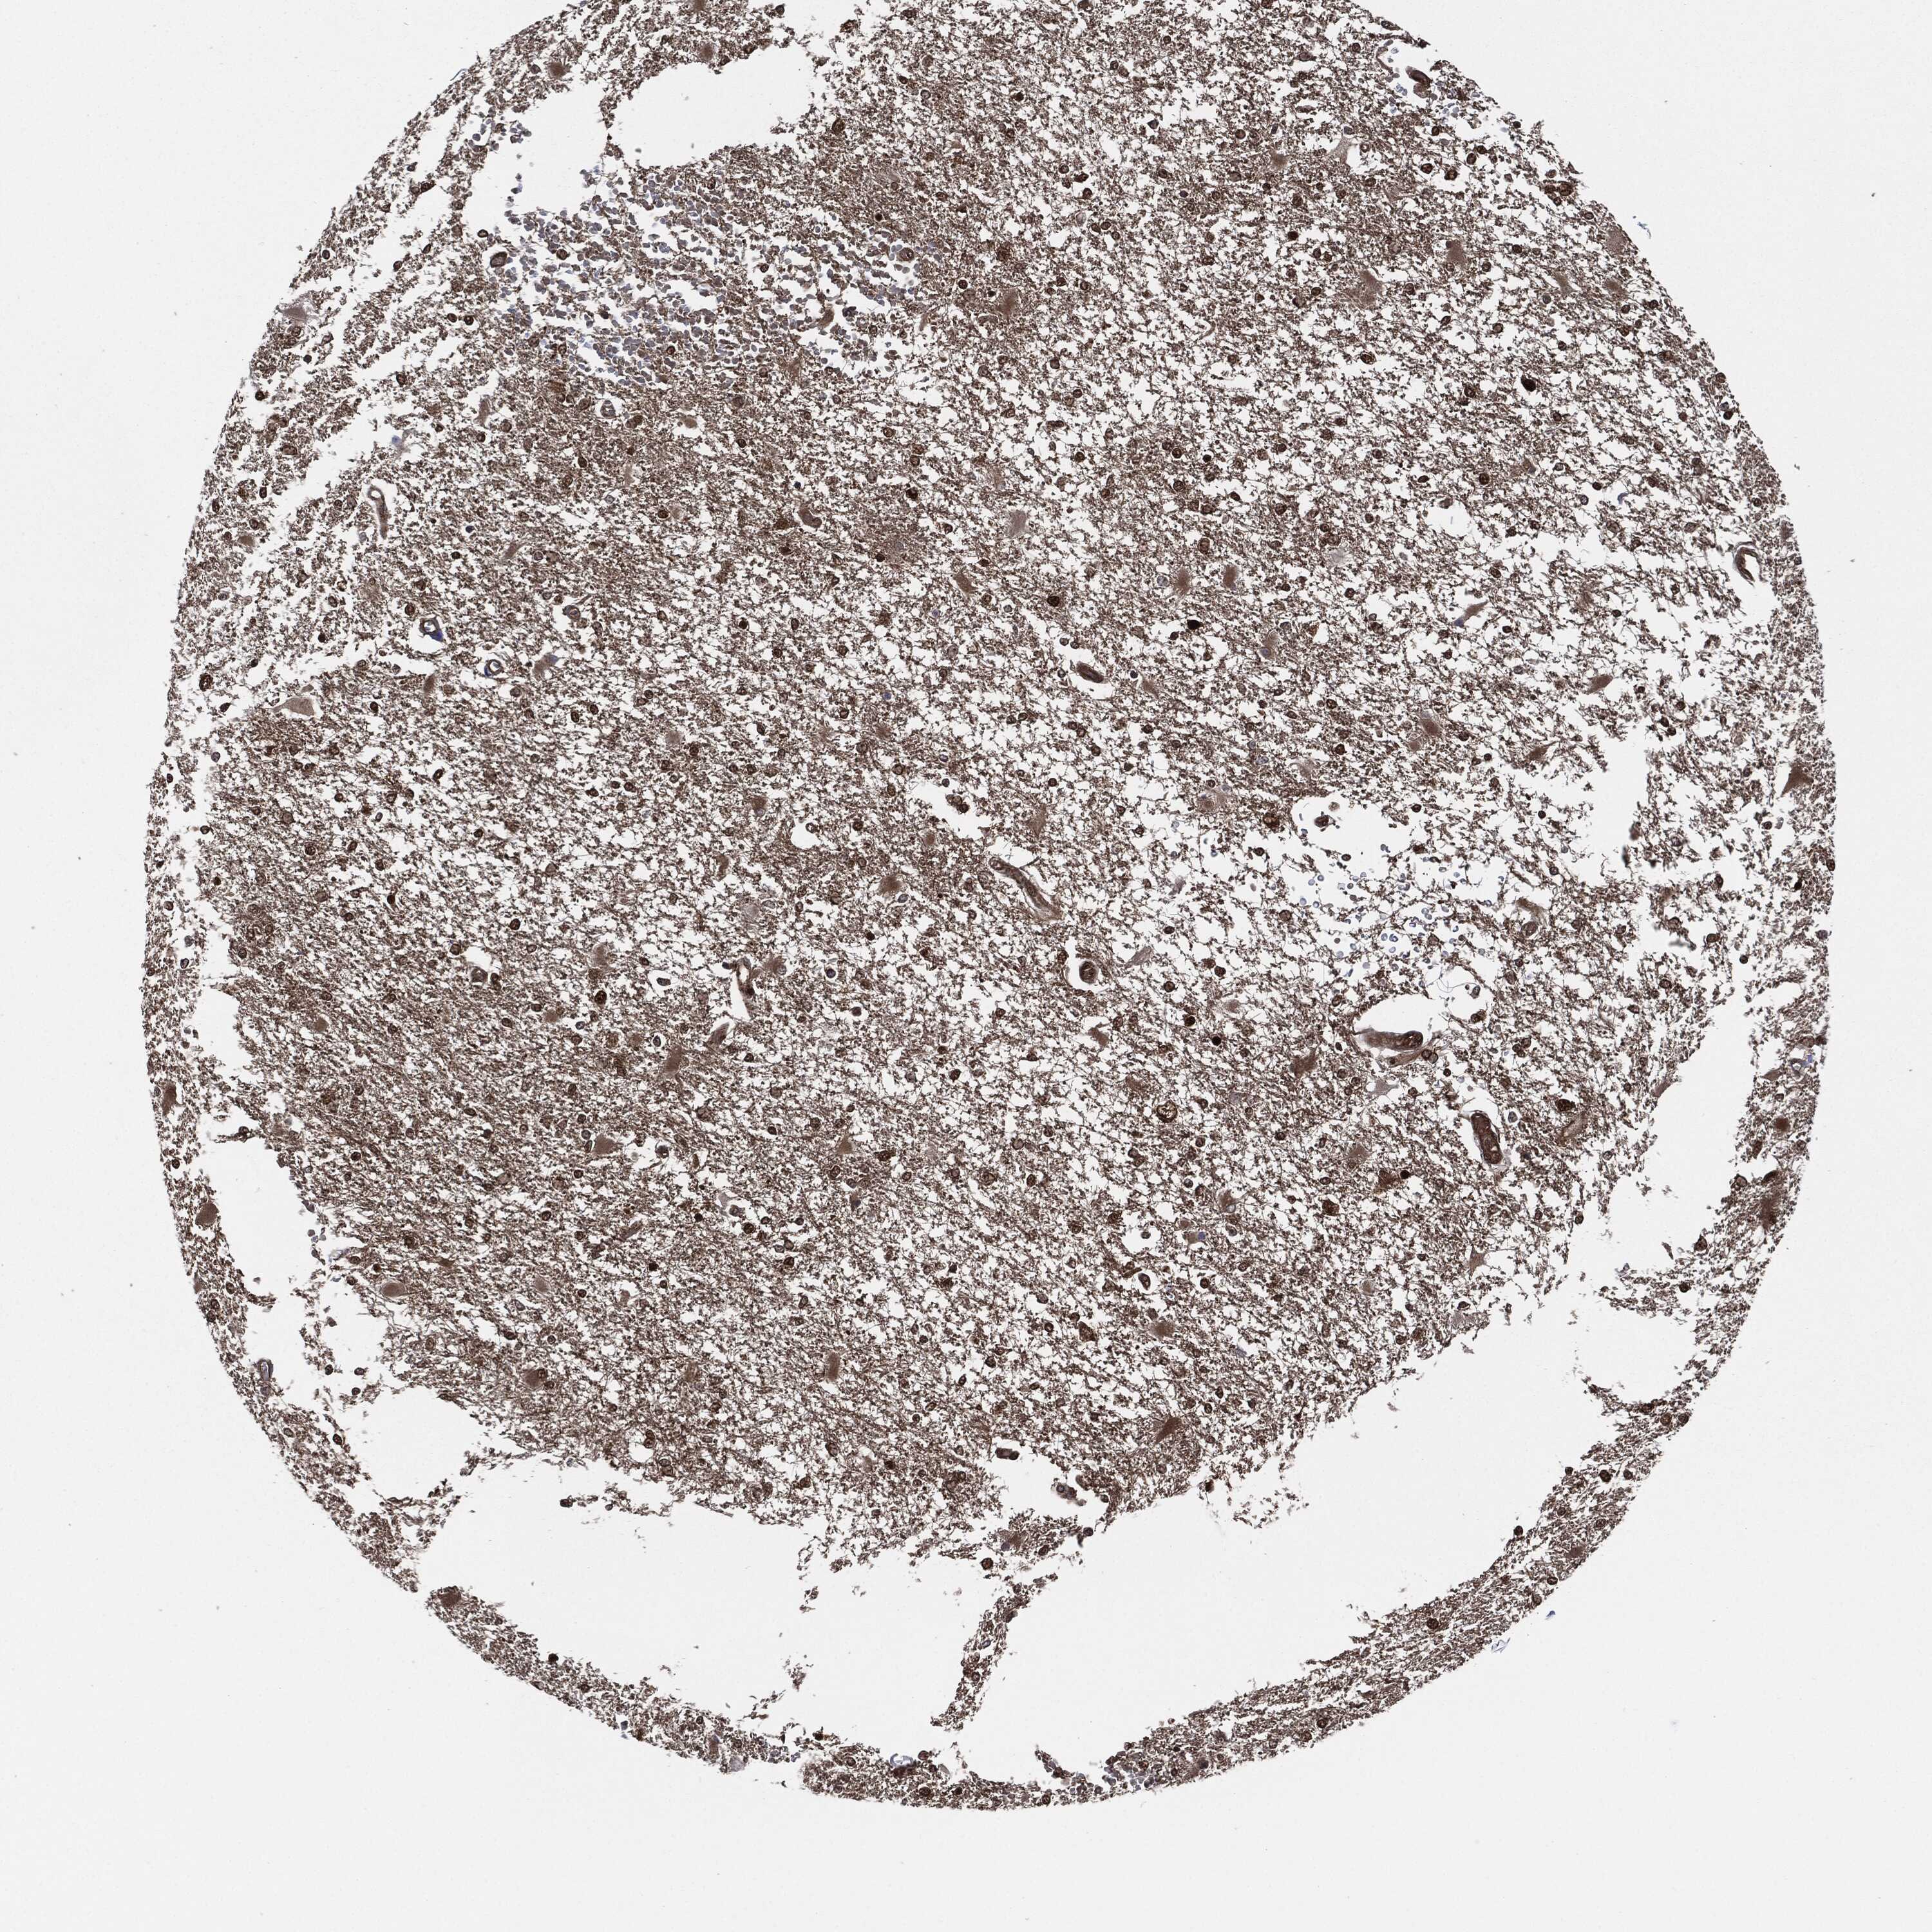

GLIOMA - Protein expressioni

A mouse-over function shows sample information and annotation data. Click on an image to view it in a full screen mode. Samples can be filtered based on level of antibody staining by selecting one or several of the following categories: high, medium, low and not detected. The assay and annotation is described here.

Note that samples used for immunohistochemistry by the Human Protein Atlas do not correspond to samples in the TCGA dataset.

Antibody stainingi

Antibody staining in the annotated cell types in the current human tissue is reported as not detected, low, medium, or high, based on conventional immunohistochemistry profiling in selected tissues. This score is based on the combination of the staining intensity and fraction of stained cells.

Each image is clickable and will lead to virtual microscopy that enables deeper exploration of all samples and also displays staining intensity scores, fraction scores and subcellular localization as well as patient and tissue information for each sample.

Antibody HPA034635

Antibody HPA069977

Antibody HPA071875

Antibody CAB009108

Staining

High

Medium

Low

Not detected

Intensity

Strong

Moderate

Weak

Negative

Quantity

>75%

75%-25%

<25%

None

Location

Nuclear

Cytoplasmic/membranous

Cytoplasmic/membranous,nuclear

Glioma, malignant, Low grade

Glioma, malignant, High grade